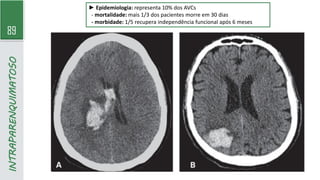

► Epidemiologia: representa 10% dos AVCs

- mortalidade: mais 1/3 dos pacientes morre em 30 dias

- morbidade: 1/5 recupera independência funcional após 6 meses